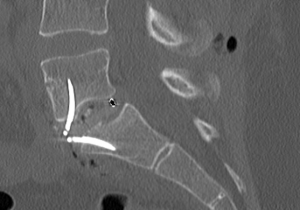

During the same operation, I then REPLACED ALL OF THE ABOVE with the following simple and elegant construct (ROI-A cage, integrated BoneCrunch fusion matrix in core; courtesy Device Technologies/LDR & AusBio/PointBlank Medical) via a minimally invasive small horizontal incision under the bikini line (anterior access provided by our technically gifted vascular surgeon). This procedure is called Anterior Lumbar Interbody Fusion (ALIF); the cage and post-op CT image is shown below: